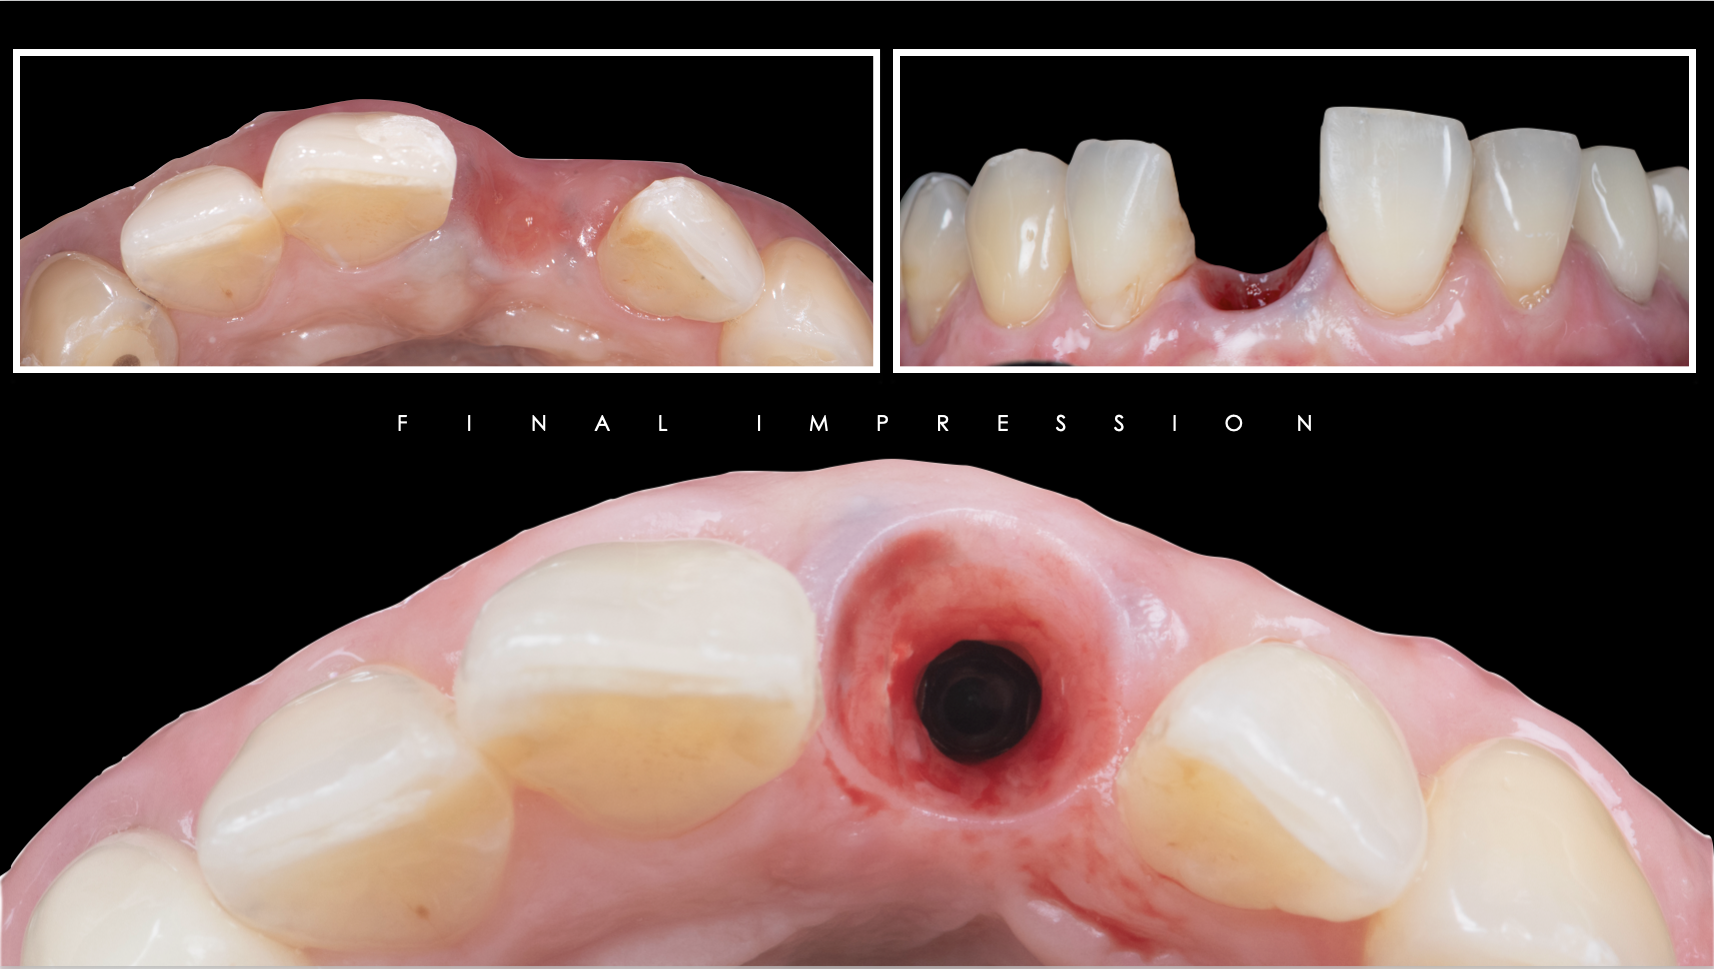

症例紹介29:インプラント治療/前歯_ソケットシール《50代女性》

治療内容:食事中に前歯が破折し、治療を希望し来院。

上顎:折れた歯を見ると、一部被せ物に歯が残っており保存不可能な状態。

上顎:歯には太い土台が入っており、折れて保存不可能な状態

リスク:残っている歯の一部を残してインプラントを入れることによって、歯茎が下がるのを抑えることができます。